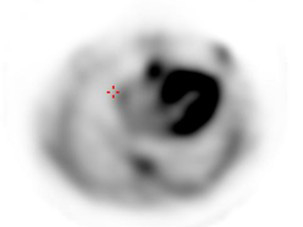

Scintigraphie cardiaque avec traceur osseux

La tomographie permet de confirmer la fixation myocardique du traceur et d’identifier une fixation faible du traceur osseux.

Conclusion :

Hyperfixation intense du traceur osseux dans le cœur grade 3 de Perugini très évocatrice d’amylose TTR en l’absence de chaines légères d’immunoglobuline.

Figure 14 : balayage corps entier

Figure 15 : acquisition tomographique